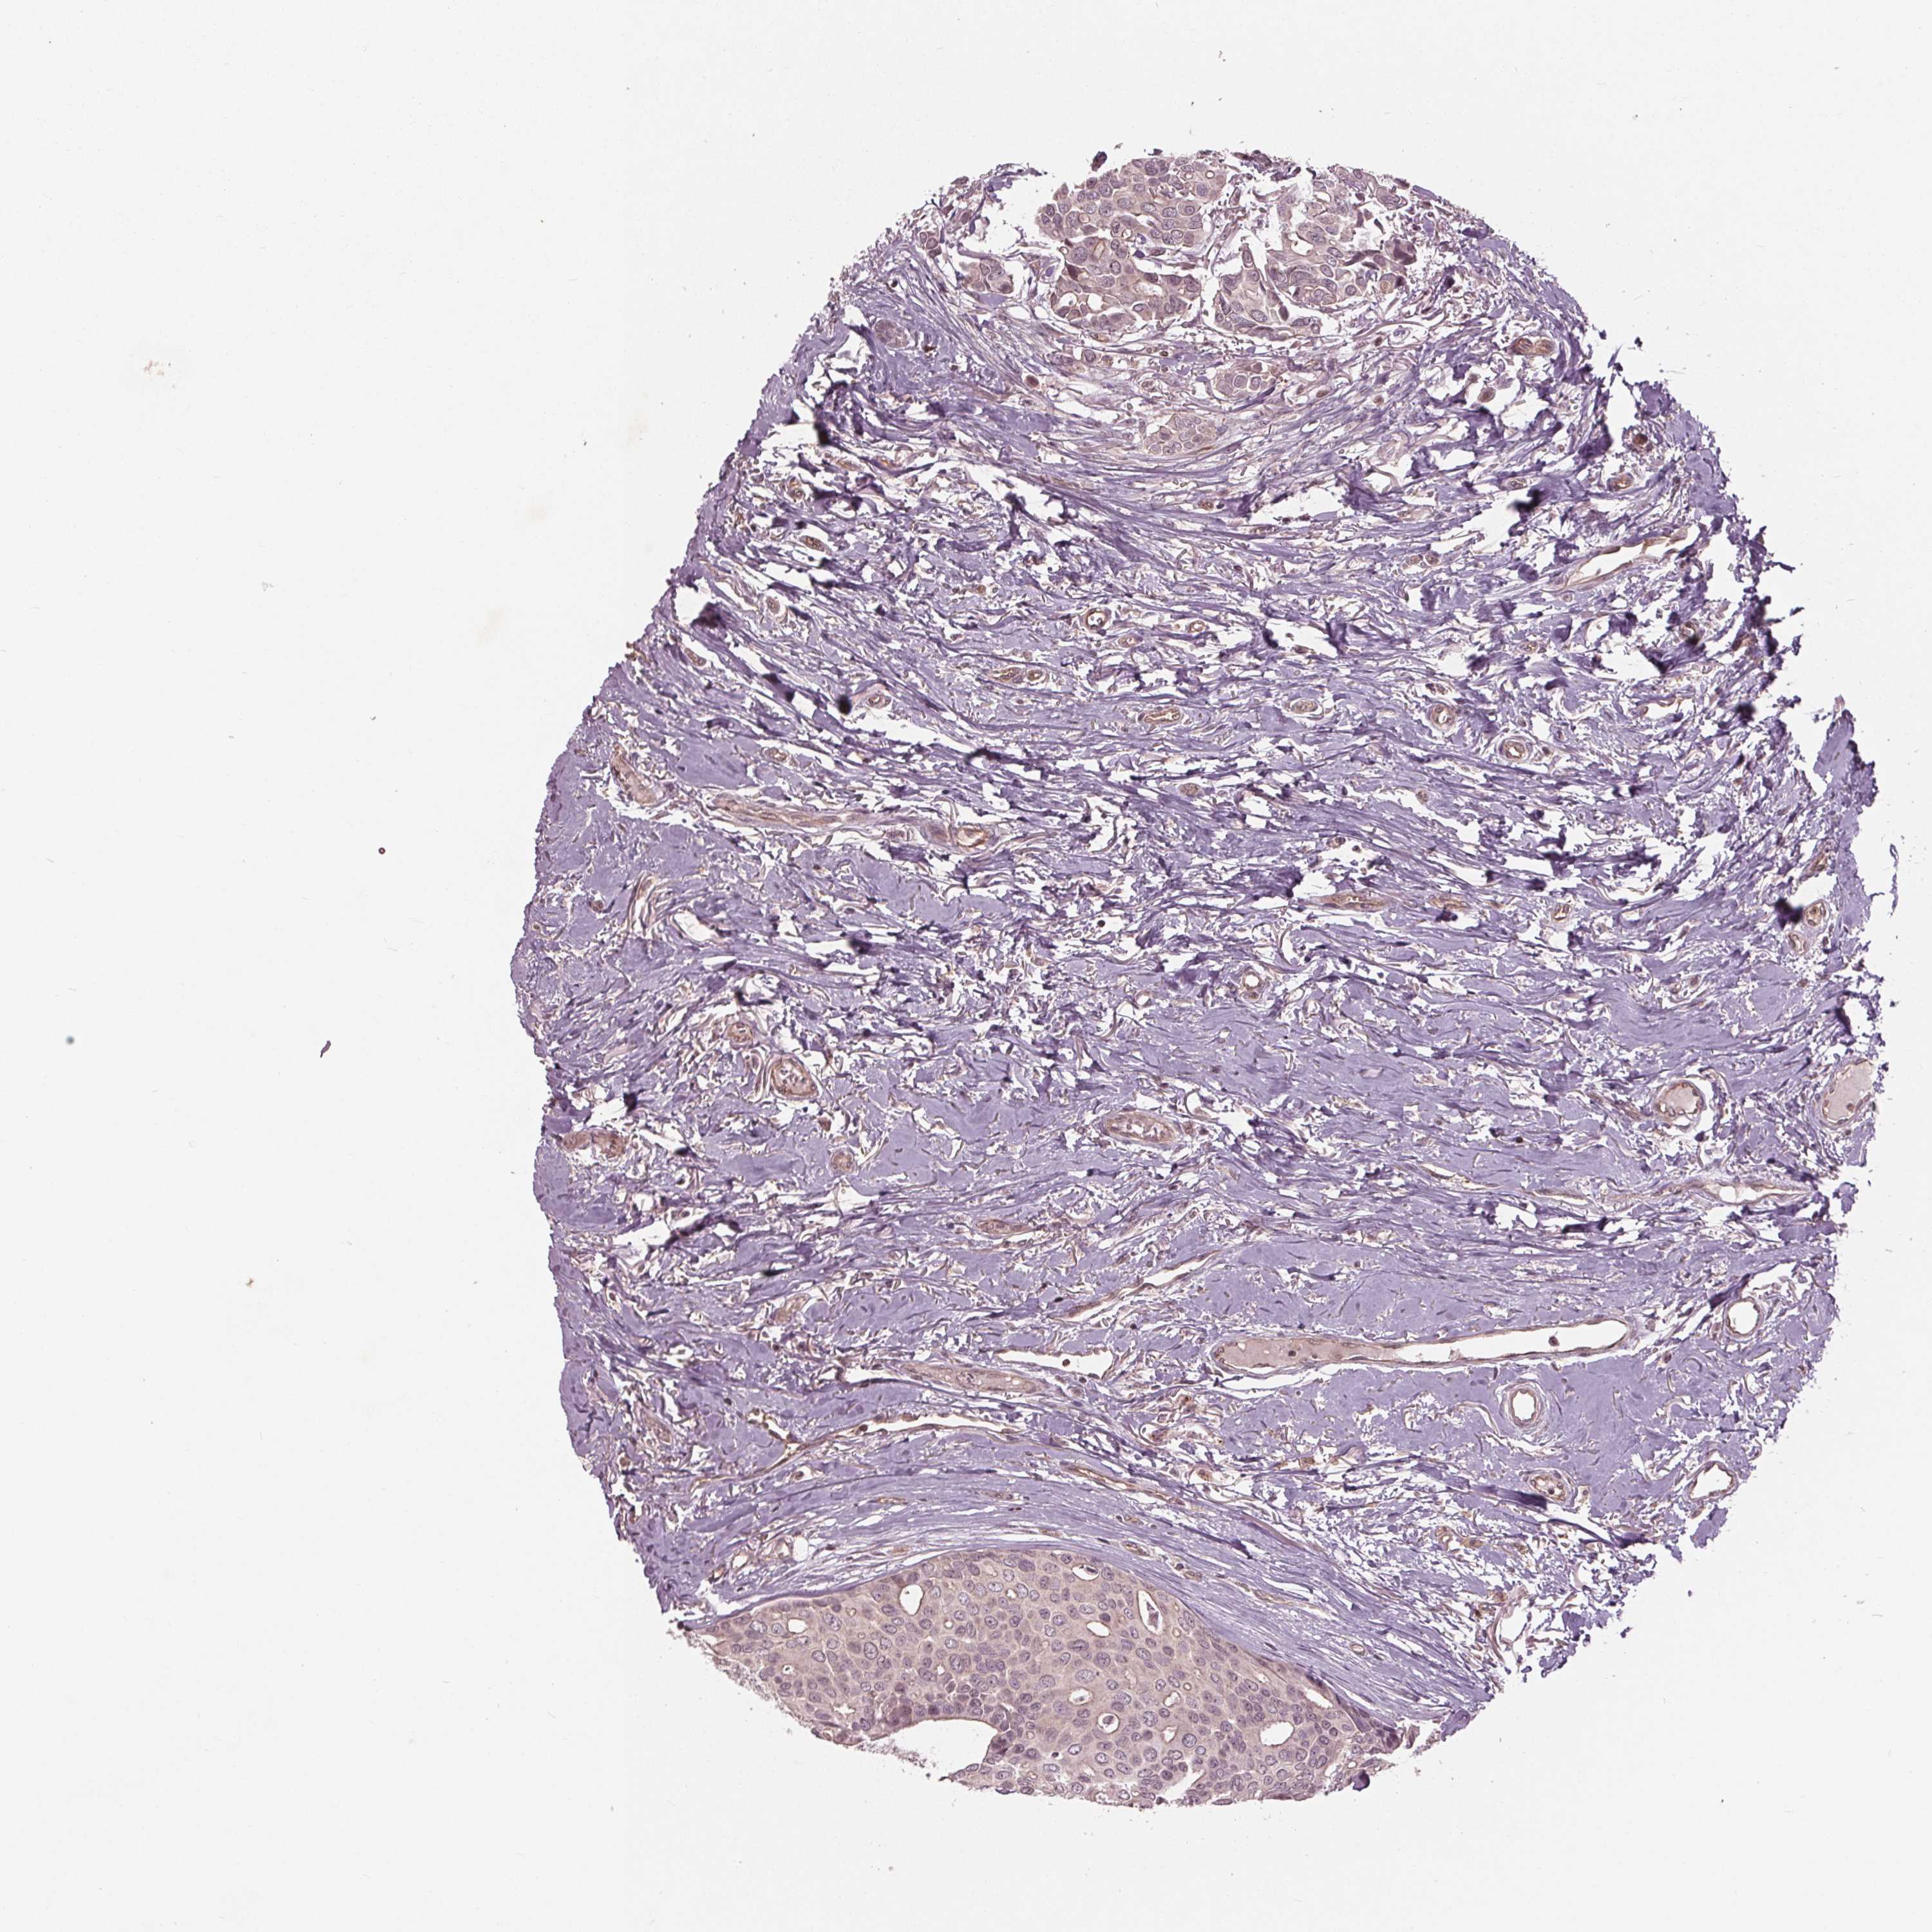

CANCER BREAST CANCER Show tissue menu

BRCA TCGA BRCA VALIDATION PROTEIN EXPRESSION

Breast cancer

Human cancer